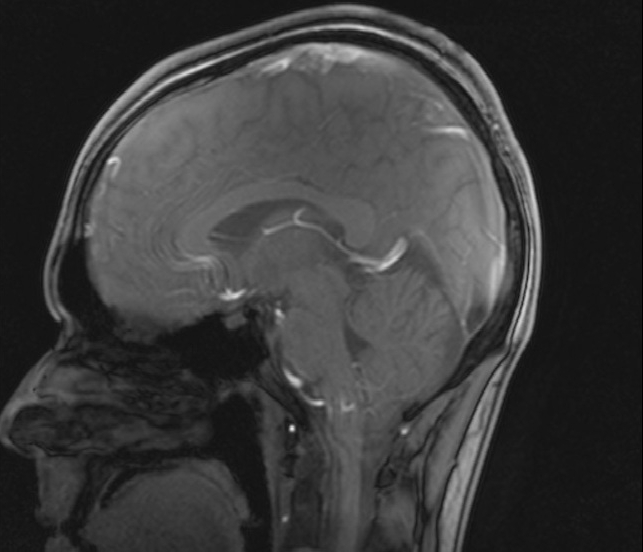

Dort würde ich Luft atmen, die statt der gewohnten 21 nur zwölf Prozent Sauerstoff enthält. Dies entspricht in etwa den Verhältnissen in einer Höhe von 4000 Metern über dem Meeresspiegel. Durch den einhergehenden Sauerstoffmangel, so die Forschungshypothese, würden die Wände der Blutgefäße des Gehirns undicht und daher Blut und Hirnwasser vermischt. Um dies zu prüfen, würden vorher und nachher MRT-Aufnahmen meines Kopfes gemacht. Bei etwa der Hälfte der Probanden sei außerdem mit Symptomen der akuten Höhenkrankheit zu rechnen.

Trotz eines leicht mulmigen Gefühls begebe ich mich also in die Sportmedizinische Ambulanz der Krehl-Klinik, es ist Samstagnachmittag. Während andere Studenten sich für das abendliche Ausgehen wappnen, lasse ich die ersten Voruntersuchungen über mich ergehen. Kurz darauf liege ich bereits zum ersten Mal in einem Tomographen. Dessen Röhre ist noch enger als ich vermutet hatte. Und laut wird es in ihr auch: Ein MRT (Magnetresonanztomograph) arbeitet mit starken Magnetfeldern. Die dafür benötigten Stromstärken produzieren einiges Geräusch. Nach einer Weile fühle ich mich, als läge ich auf einem U-Bahn-Schacht.

Am nächsten Morgen sehne ich die abschließende MRT-Aufnahme förmlich herbei. Mittlerweile ist mir vollauf bewusst, wofür man das scheinbar leicht verdiente Probandenentgelt erhält. Nicht dass ich meine Teilnahme an der Studie bereuen würde, aber erneut teilnehmen werde ich wohl nicht. Kurz darauf werde ich in einem Rollstuhl Richtung MRT geschoben, neben mir ein riesiger Blasebalg. Durch diesen werde ich auch weiterhin mit sauerstoffarmer Luft beatmet. In den Gängen der Klinik werde ich misstrauisch beäugt; ich muss ziemlich miserabel aussehen. Eine halbe Stunde später jedoch ist alles überstanden. Zum ersten Mal seit zwölf Stunden kann ich wahrhaft durchatmen. Ein wunderschönes Gefühl. Nach diesem Erlebnis beschleicht mich jedoch erneut die Frage: Wozu das Ganze? Wofür, außer als neues Facebook-Profilbild, taugen 2000 Fotos meines Gehirns? Kurz: Hat sich der Aufwand gelohnt?